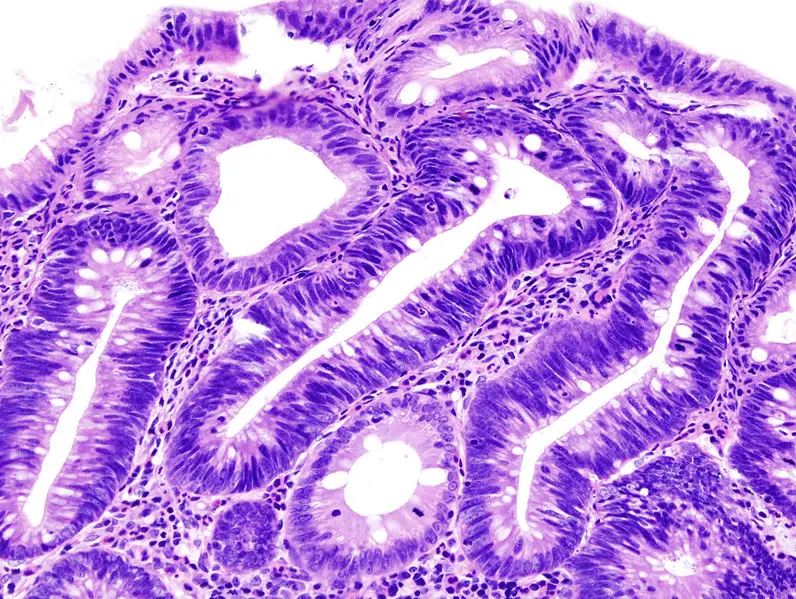

Che cos’è l’adenocarcinoma Gli adenocarcinomi sono tumori indifferenziati e maligni, le tipologie che insorgono nel contesto dell’ esofago di Barrett sono generalmente localizzati nell’esofago distale e possono invadere il cardias adiacente. ...

Cos’è l’adenoma Gli adenomi sono dei tumori benigni che originano in tessuti con proprietà secretorie e che assumono l’aspetto di una ghiandola. Nello specifico, gli adenomi possono trarre origine dalle cellule epiteliali degli organi...